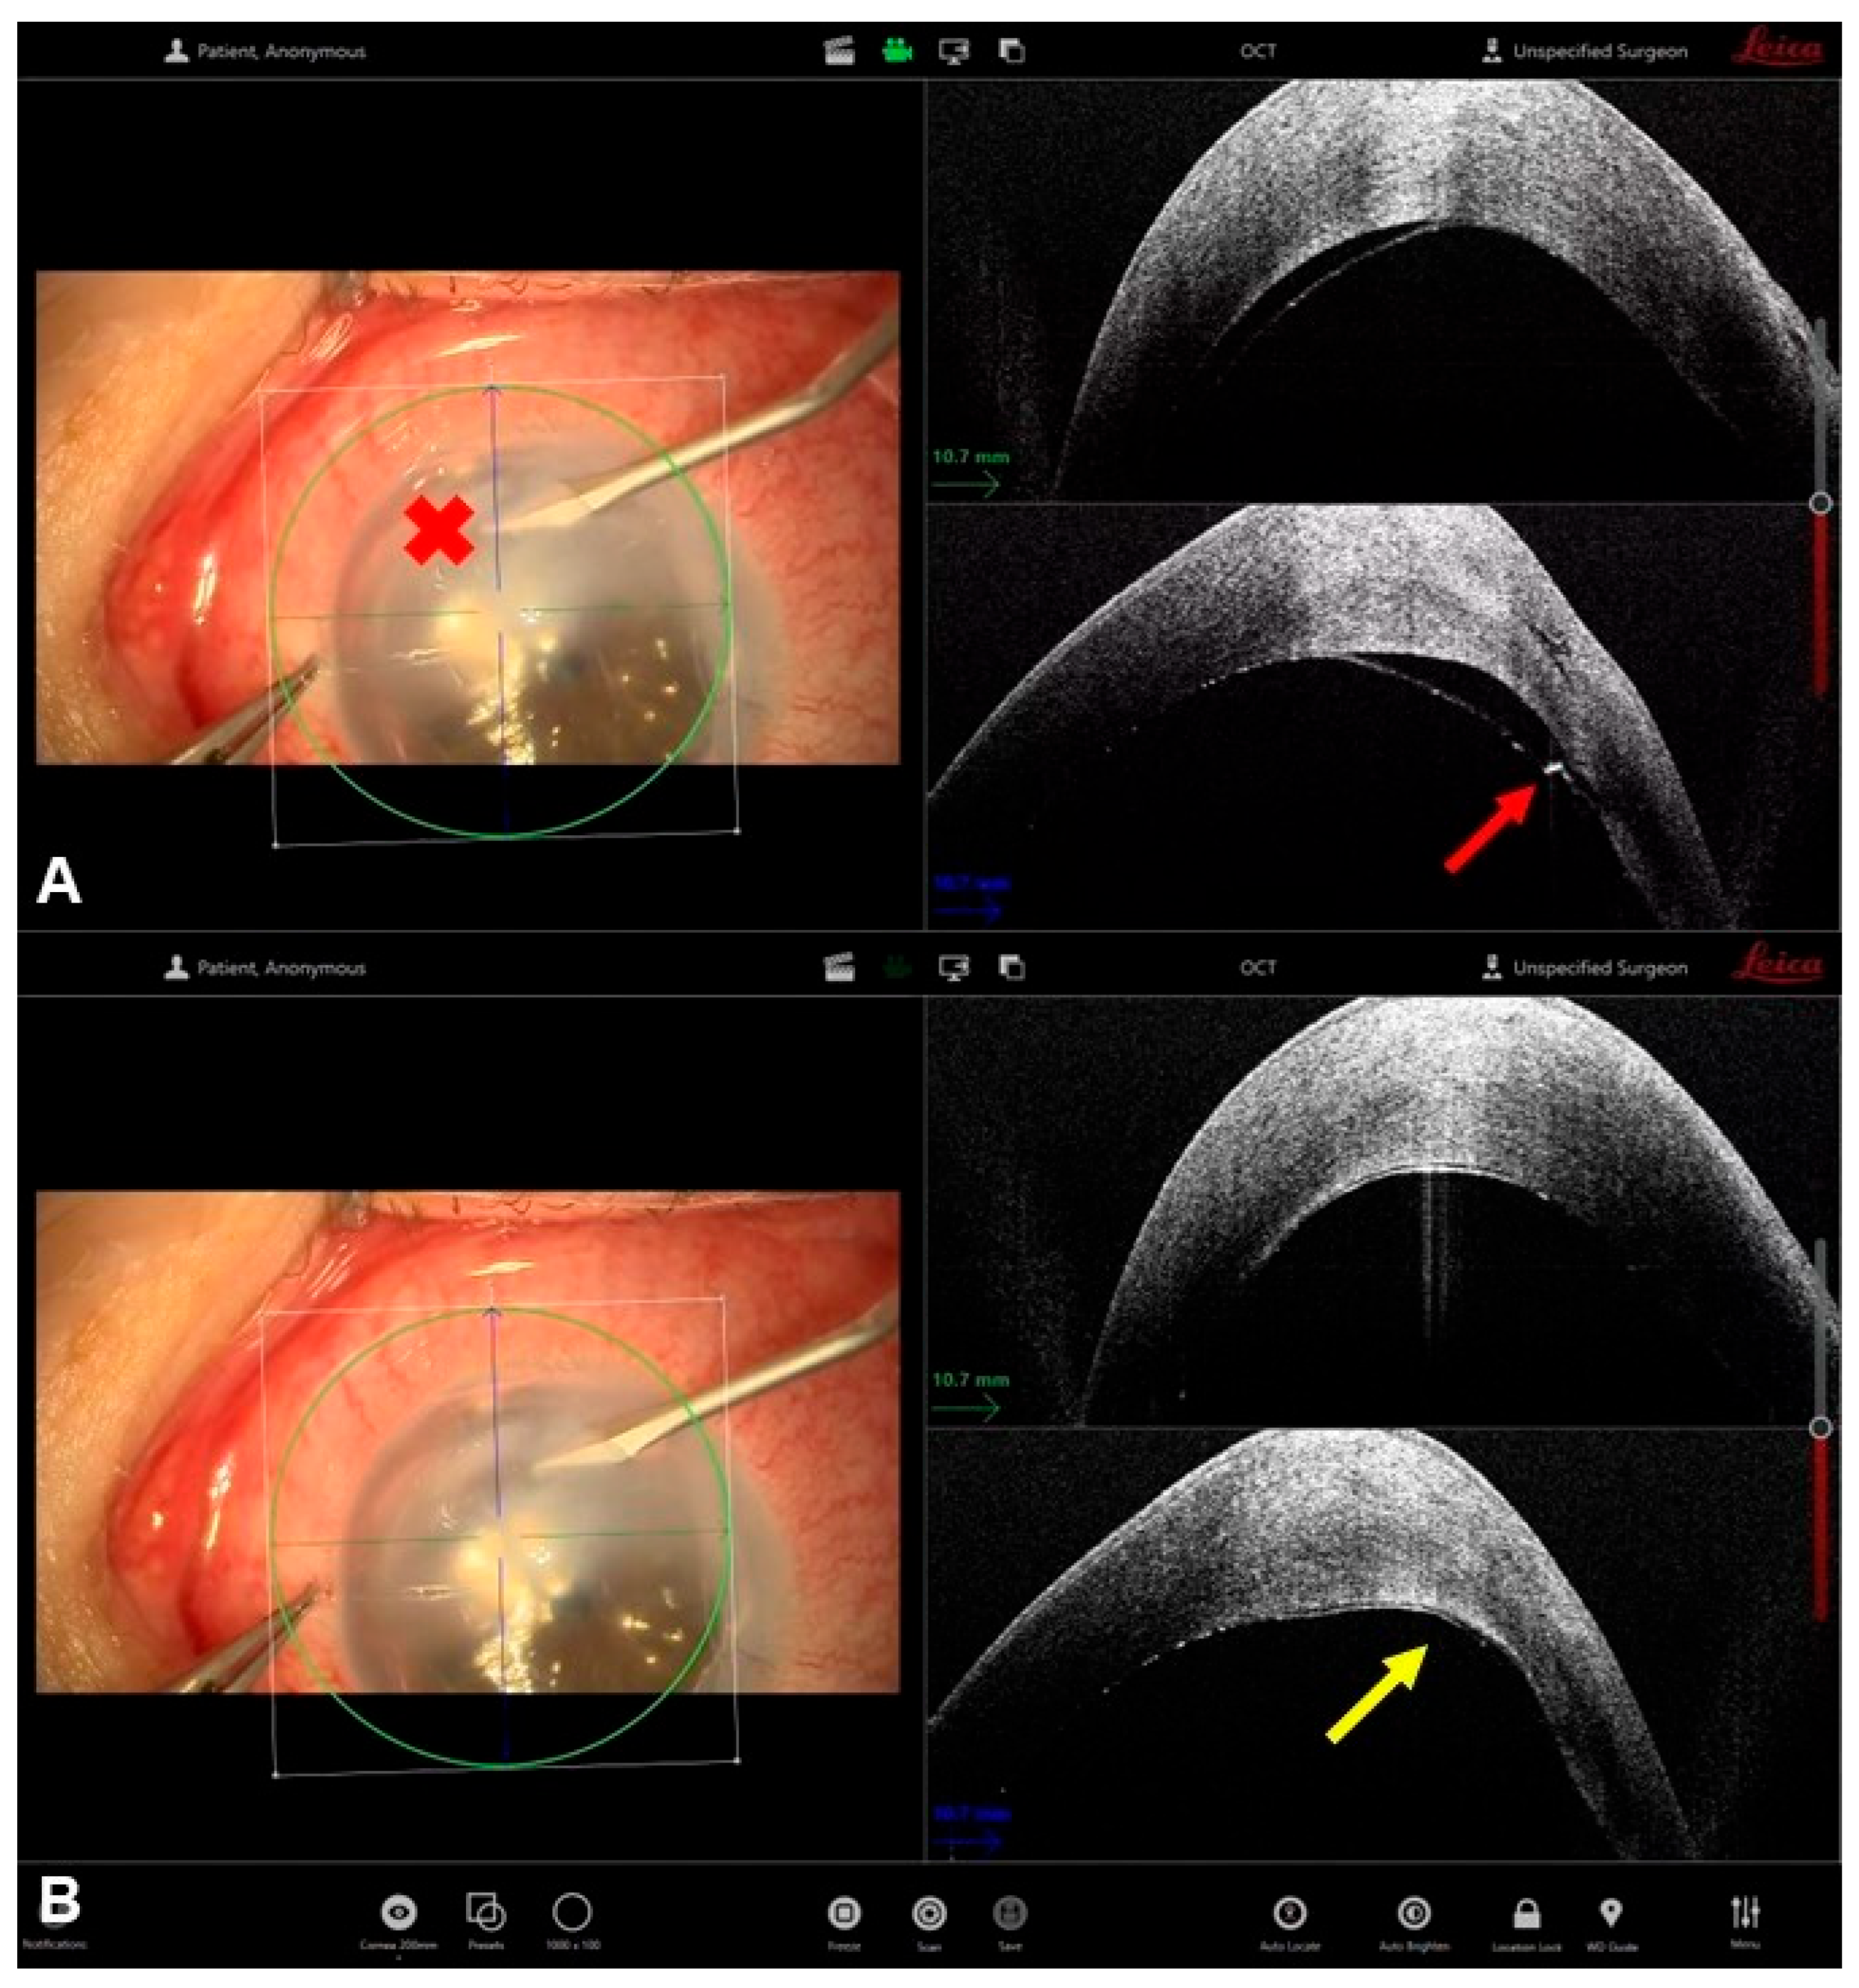

- Moramarco, A.; Elifani, M.; Zimbru, M.S.; Rosolia, A.; Mete, M.; Fontana, L. Air-Assisted Dome Drainage in Acute Corneal Hydrops: A 3D-OCT-Guided Approach. Bioengineering 2025, 12, 867. [Google Scholar] [CrossRef] [PubMed]

- Siebelmann, S.; Händel, A.; Matthaei, M.; Bachmann, B.; Cursiefen, C. Microscope-Integrated Optical Coherence Tomography-Guided Drainage of Acute Corneal Hydrops in Keratoconus Combined With Suturing and Gas-Aided Reattachment of Descemet Membrane. Cornea 2019, 38, 1058–1061. [Google Scholar] [CrossRef]

- Kaur, M.; Balaji, A.; Titiyal, J.S.; Bansal, M.; Raj, R.; Namdev, V. Intraoperative optical coherence tomography-guided compression sutures in acute corneal hydrops-Surgical technique and review of literature. Indian J. Ophthalmol. 2025. Epub ahead of print. [Google Scholar] [CrossRef] [PubMed]

| Moramarco et al. [29] | Case series | 6 eyes | Corneal hydrops drainage | Controlled drainage of the stromal dome with a 23-gauge sclerotome, with dynamic monitoring of fluid outflow |

| Siebelmann et al. [30] | Case series | 2 patients | Corneal hydrops drainage | iOCT-guided puncture and drainage of intrastromal fluid pockets combined with anterior chamber sulfur hexafluoride-fill and pre-descemetic sutures |

| Kaur et al. [31] | Prospective interventional case series | 7 patients | Corneal hydrops drainage | Assess the morphological features of the hydrops, titrate the magnitude of suture tightness and confirm the depth of suture placement |